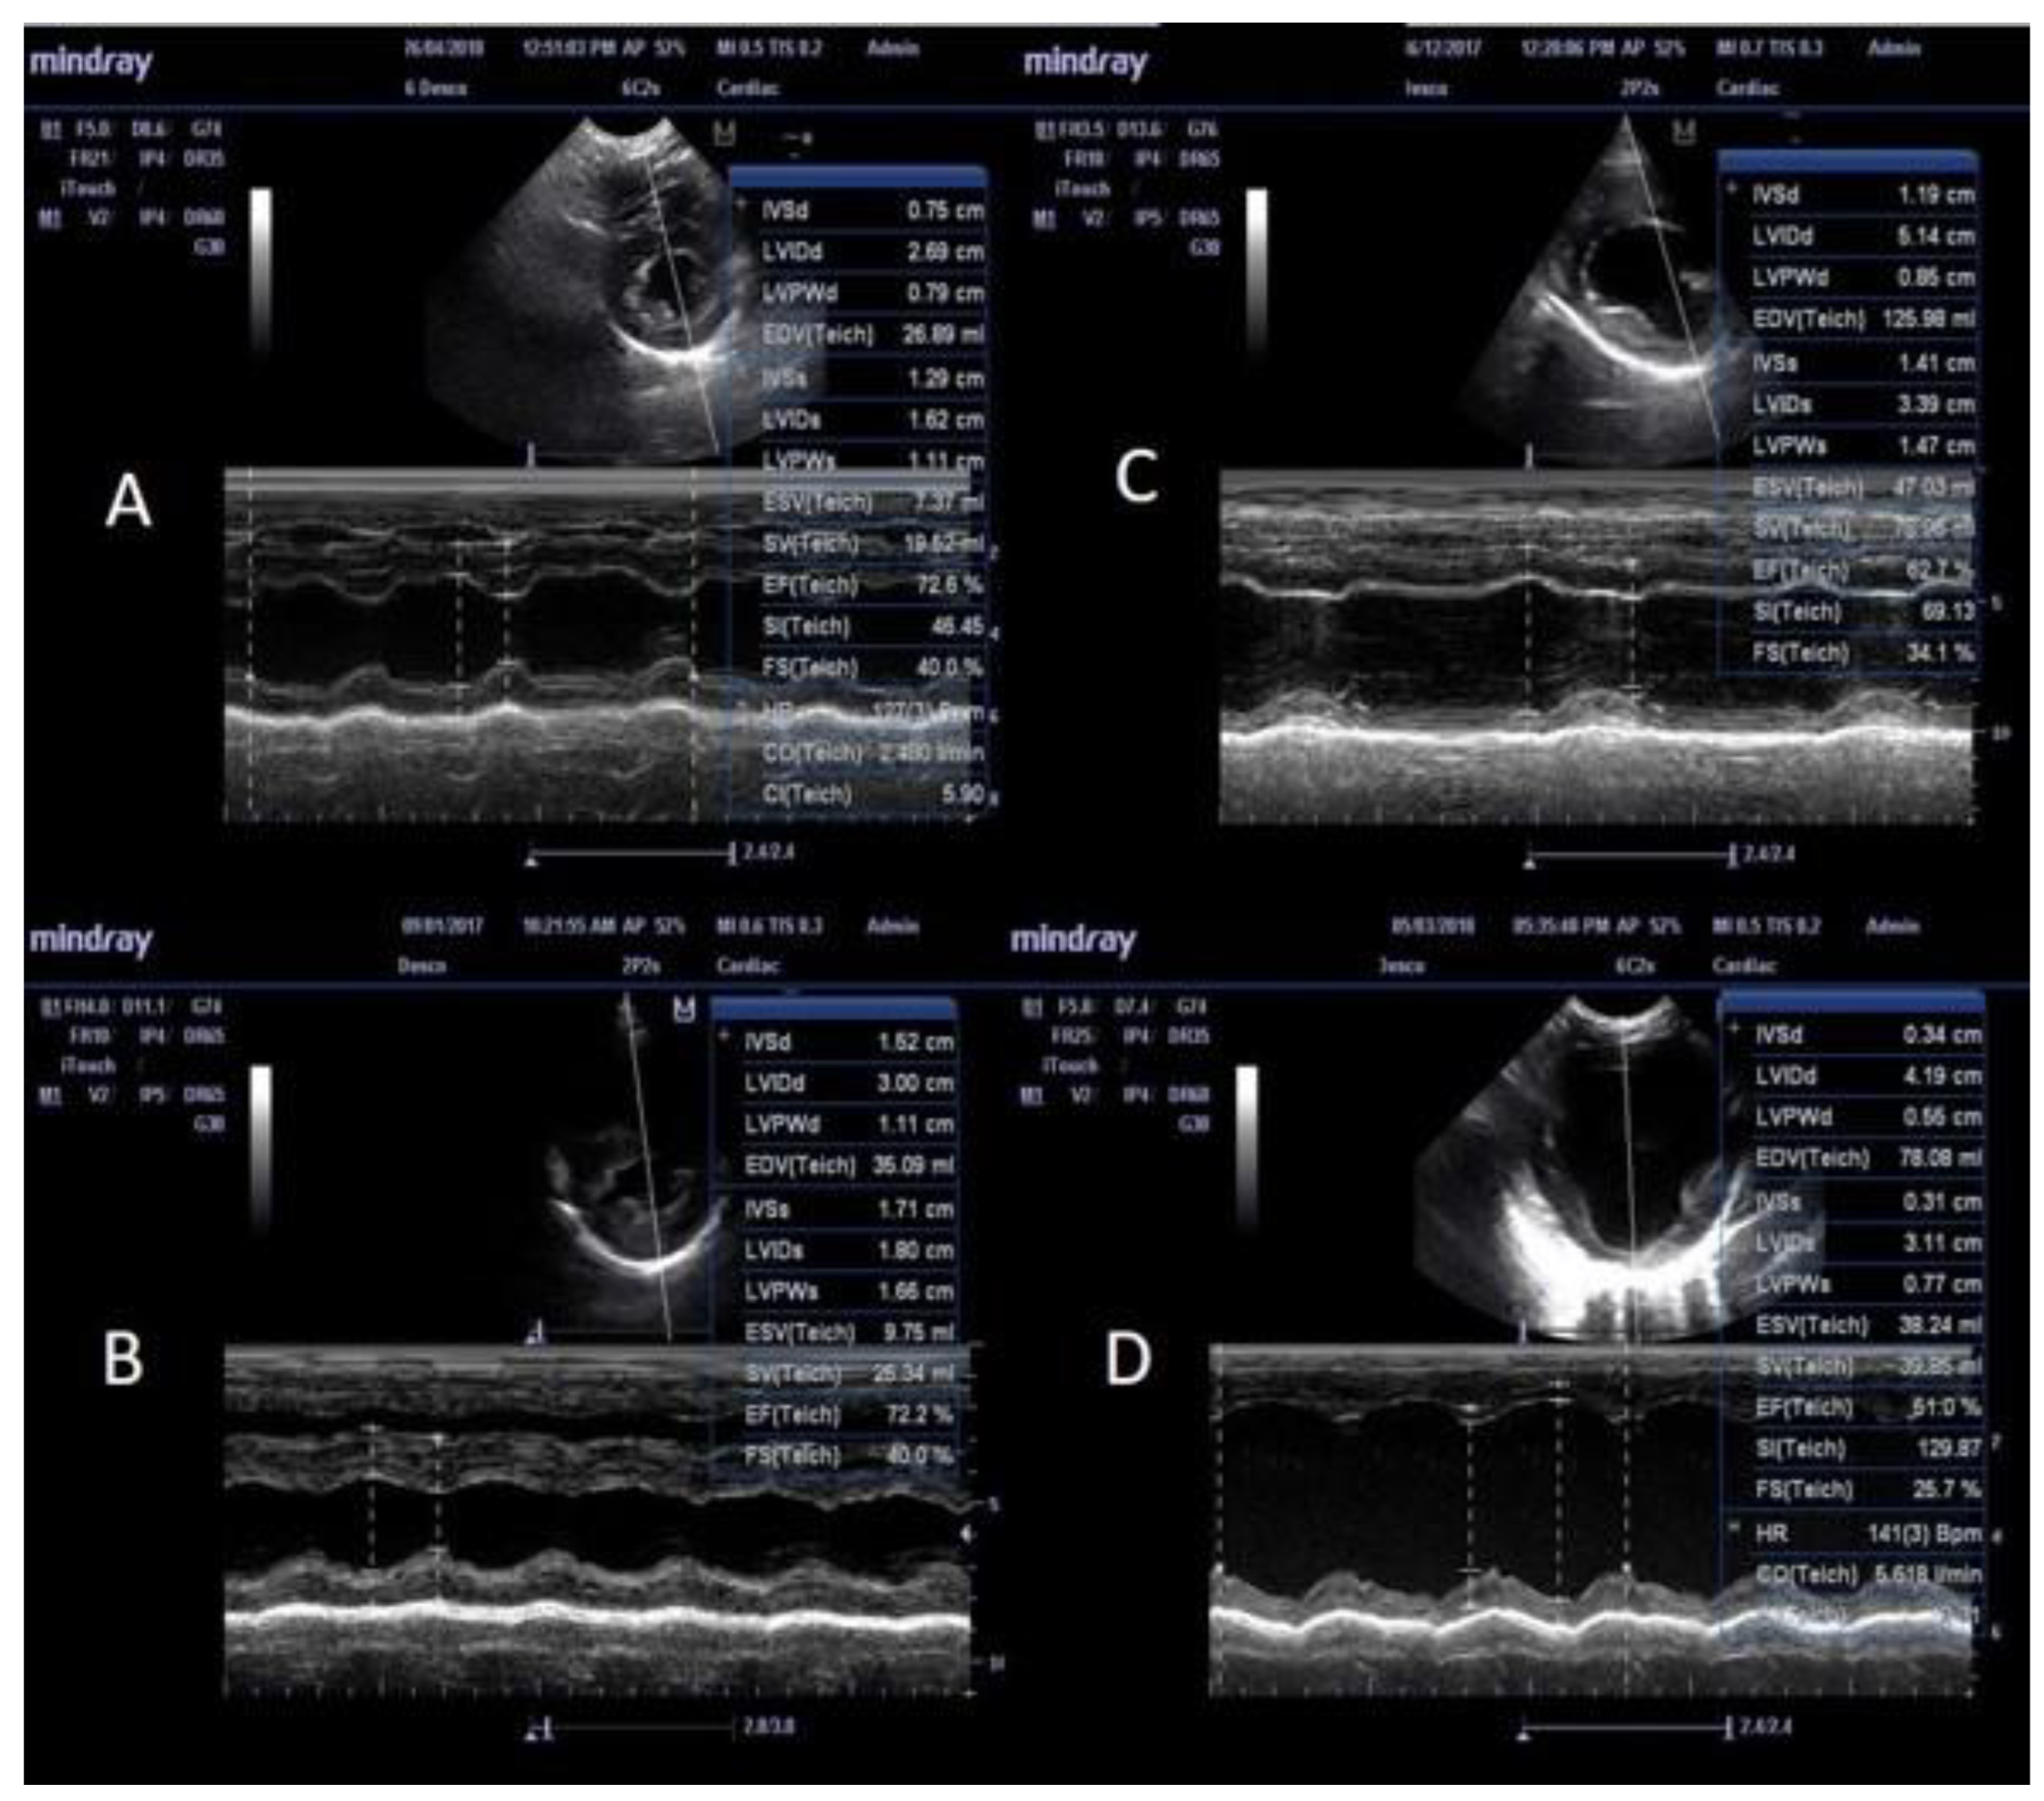

3.3. M-Mode Ultrasonographic Findings

| Parameters | Mode | A (n= 23) | Aw (n= 3) | B (n= 6) | C (n= 86) | Cw (n= 12) | Controls (n=16) |

| A: Structural features | |||||||

| IVS diastole (IVS-d)* 1 | M mode | 0.5 ± 0.07 a | 0.51 ± 0.05 | 0.4 ± 0.08 | 0.49 ± 0.08 b | 0.4 ± 0.08 a, b | 0.44 ± 0.07 |

| IVS systole (IVS-s)* 1 | M mode | 0.69 ± 0.01 | 0.66 ± 0.05 | 0.67 ± 0.17 | 0.7 ± 0.15 | 0.64 ± 0.18 | 0.64 ± 0.09 |

| LVID diastole (LVID-d)* 2 | M mode | 1.44 ± 0.24 a, | 2.02 ± 0.16 a, b | 1.57 ± 0.20 b, c | 1.35 ± 0.25 b, c, d | 2.05 ± 0.15a ,c ,d, e | 1.55 ± 0.1 b, d, e |

| LVID systole (LVID-s)* 2 | M mode | 0.83 ± 0.18 a | 1.15 ± 0.10 a, b | 0.91 ± 0.13 c | 0.76 ± 0.2 b | 1.23 ± 0.19 a, c | 0.86 ± 0.1 b |

| LVPW diastole (LVPW-d)* 2 | M mode | 0.51 ± 0.09 a | 0.39 ± 0.16 a | 0.34 ± 0.03 a, b | 0.49 ± 0.1 b, c, d | 0.4 ± 0.09 a, c, d, e | 0.47 ± 0.06 b, d, e |

| LVPW systole (LVPW-s)*2 | M mode | 0.71 ± 0.09 a | 0.62 ± 0.18 | 0.53 ± 0.11 a, b | 0.73 ± 0.12 b | 0.69 ± 0.19 b | 0.68 ± 0.08 b |

| EPSS 1 | M mode | 0.39 ± 0.21a | 0.93 ± 0.13 b | 0.5 ± 0.2 | 0.31 ± 0.21 b, c | 0.96 ± 0.09 a, c, d | 0.27 ± 0.11 b, d |

| LA/Ao 1 | B mode | 1.39 ± 0.51 a | 1.69 ± 0.51 | 1.38 ± 0.17 | 1.25 ± 0.24 b | 1.86 ± 0.43 a, b, c | 1.19 ± 0.14 c |

| SI 1 | B & M mode | 1.99 ± 0.21 a | 1.54 ± 0.1 b | 1.87 ± 0.19 | 1.97 ± 0.24 b, c | 1.53 ± 0.08 a, c | 1.75 ± 0.07 a, c |

| B: Functional features | |||||||

| Fractional shortening (FS), %** 1 | M mode | 40.35 ± 6.66 | 40.33 ± 5.69 | 38.83 ± 5.03 | 41.39 ± 11.2 | 37 ± 10.72 | 41.75 ± 5.36 |

| Ejection fraction (EF), %** 1 | M mode | 72.61 ± 7.69 | 71.2 ± 7.30 | 68.33 ± 7.51 | 72.75 ± 12.58 | 64.17 ± 14.1 | 74.09 ± 6.68 |

| Stroke volume (SV), mL** 1 | M mode | 20.85 ± 14.37 a | 33.52 ± 14.77 | 27.49 ± 26.35 | 22.17 ± 15.5 b | 51.18 ± 28.4 a, b | 24.01 ± 10.97 |

| Heart rate 1 | M mode | 102.43 ± 17.98 | 121 ± 8.54 | 95.33 ± 8.71 | 102.5 ± 31.57 | 121.25 ± 41.29 | 108.75 ± 23.95 |

| Cardiac output (CO), L/min** 1 | M mode | 2.1 ± 1.31 a | 4 ± 1.53 | 2.63 ± 2.52 | 2.22 ± 1.55 b | 6.6 ± 5.13 a, b | 2.46 ± 0.81 |